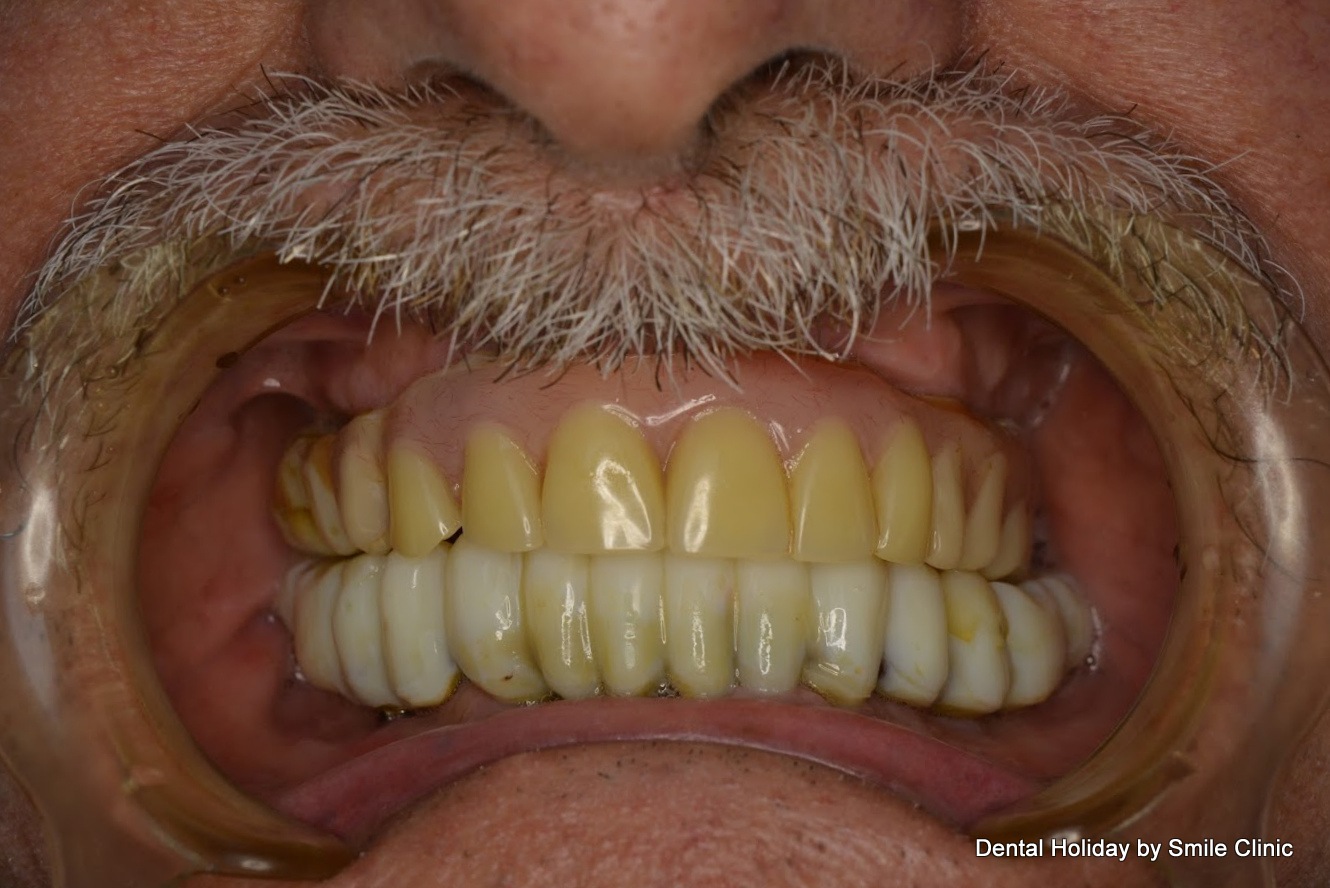

The patient came back in 3 months. His dental implants were safely healed within his bone and we were able to take impressions. Thanks to the impressions our dental technicians made Alan’s final dental bridges.

On the third visit, we finished Alan’s dental treatment. We removed his temporary dental crowns and put 14 porcelain dental crowns on his upper jaw and 14 dental crowns on his lower jaw.